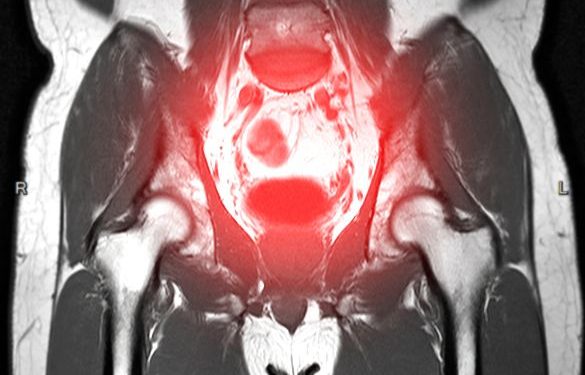

Liver problems are often diagnosed through physical examination and lab tests. Some of these tests include hepatitis C antibodies, liver function tests, and a complete blood count. Other tests may include imaging such as a CT scan, MRI, ultrasound or liver biopsy.